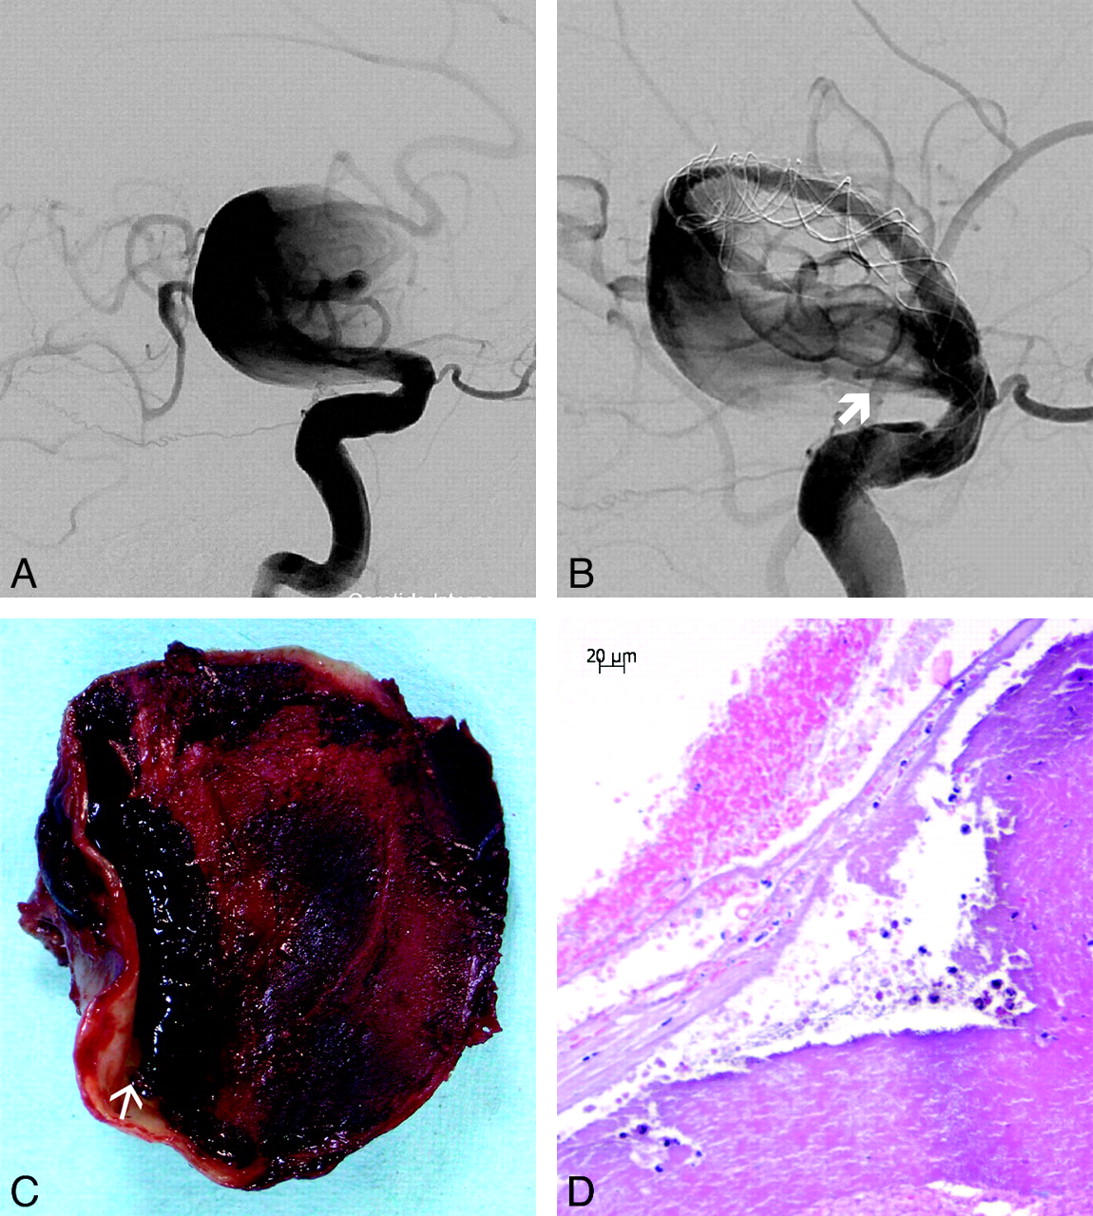

Patient No. 6. A and B, Posteroanterior view DSA image of a symptomatic fusiform aneurysm of the basilar trunk (A) and lateral view after FD treatment (B) demonstrate contrast stasis in the aneurysm. C, 3D CT angiogram obtained 3 days after treatment shows patency of the basilar trunk and lack of aneurysm filling. D, Macroscopic view of the basilar artery and aneurysm after postmortem examination shows a massive thrombus volume bulging through the aneurysm wall defect. E, HE-stained microscopic view of the edge of the aneurysm wall rupture shows a partially maintained but vanishing adventitia (black arrow) and disappearance of the vascular tunica media (white arrow).

Patient No. 5. A and B, Giant fusiform aneurysm of the right distal ICA, right oblique view before (A) and after FD implantation, with a persisting inflow jet (thick arrow) (B). C, Cross-section of the aneurysm after postmortem examination shows organized thrombus filling most the aneurysm lumen. Note a dissecting cavity with liquefied clot between the organized thrombus and the thick part of the aneurysm wall (arrow). D, Microscopic view of the aneurysm after HE-staining at the rupture site shows necrosis and almost complete disappearance of the aneurysm wall.